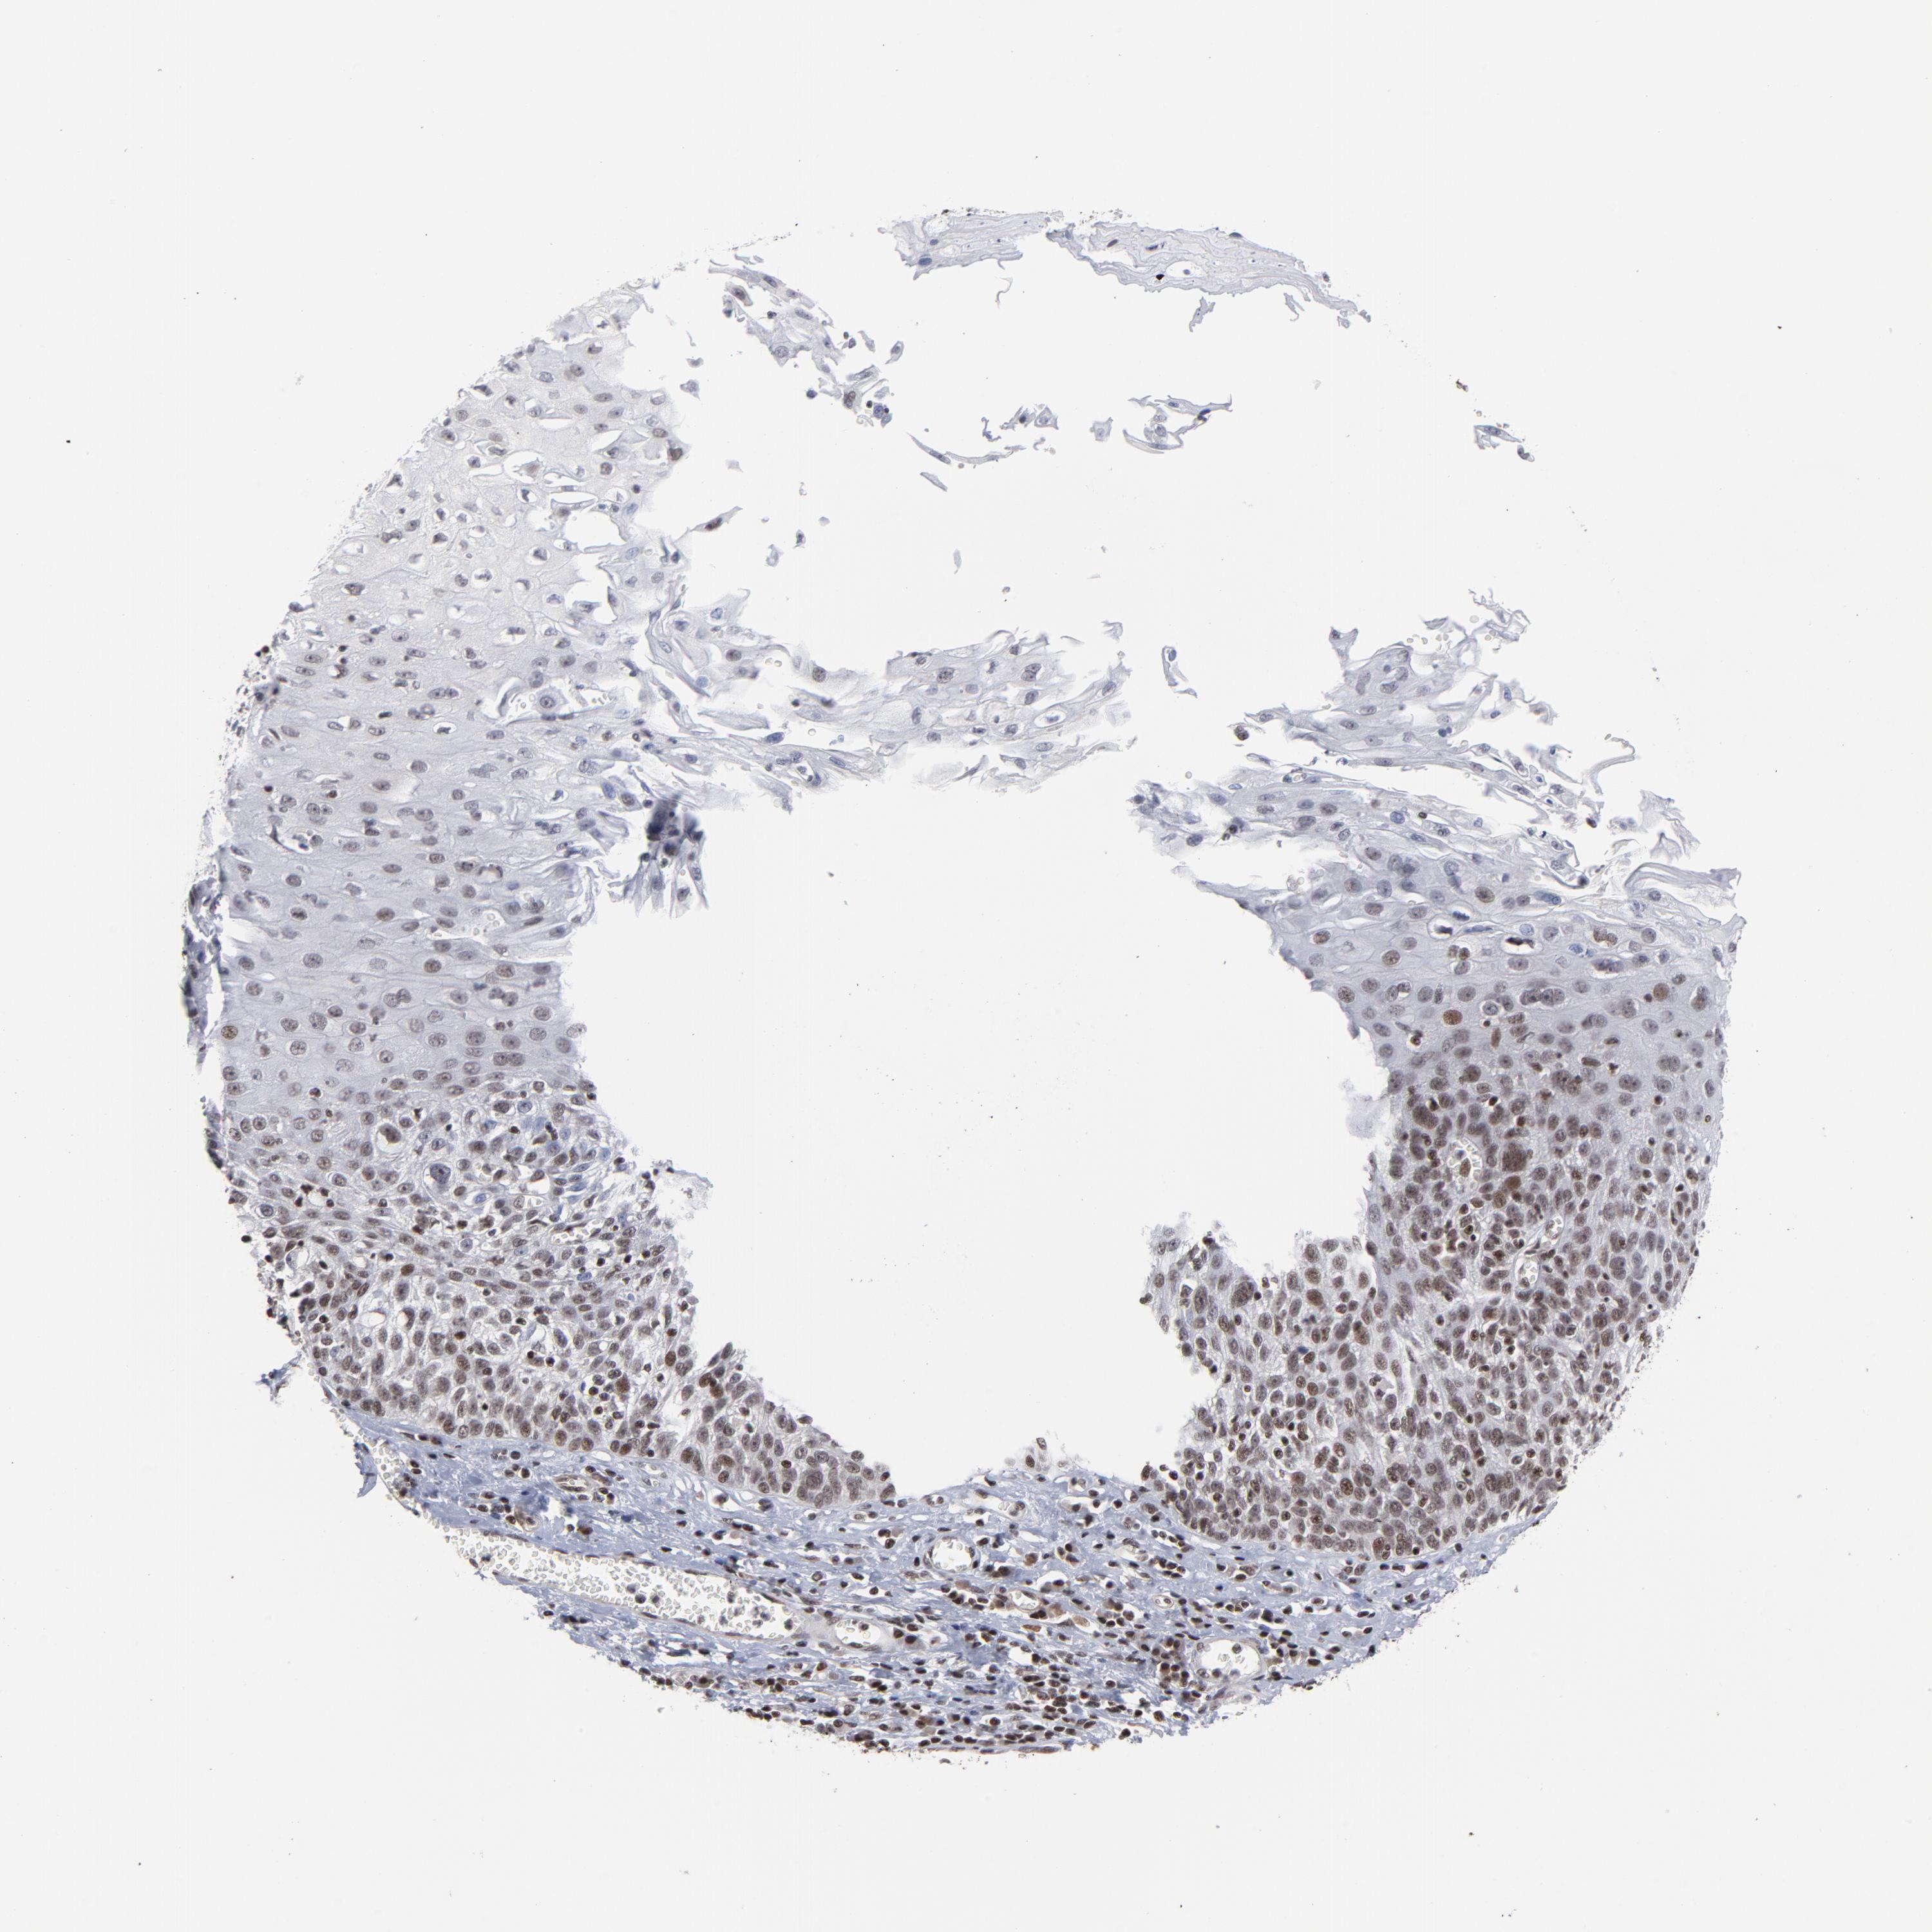

ESOPHAGUS - Antibody stainingi

Antibody staining in the annotated cell types in the current human tissue is reported as not detected, low, medium, or high, based on conventional immunohistochemistry profiling in selected tissues. This score is based on the combination of the staining intensity and fraction of stained cells.

Each image is clickable and will lead to virtual microscopy that enables deeper exploration of all samples and also displays staining intensity scores, fraction scores and subcellular localization as well as patient and tissue information for each sample.

Antibody HPA004122Antibody CAB062550Antibody CAB068181Antibody CAB068182

Squamous epithelial cells HighMediumHighHigh